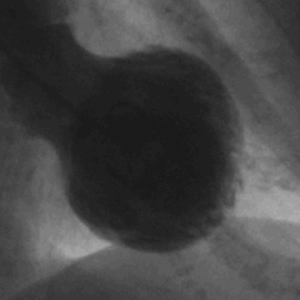

La cateterización cardíaca urgente es otro paso clave en el diagnóstico. Este procedimiento generalmente muestra un abultamiento en el área apical del ventrículo izquierdo, mientras que las coronarias suelen aparecer normales. Este hallazgo es crítico, ya que ayuda a diferenciar la cardiopatía de Takotsubo de un infarto de miocardio causado por enfermedad arterial coronaria, donde se esperaría ver obstrucciones significativas.

La cardiopatía de Takotsubo, también conocida como síndrome del corazón roto, es una condición clínica caracterizada por un debilitamiento temporal del músculo cardíaco que se presenta de manera aguda, y que se asocia frecuentemente con episodios de estrés emocional o físico intenso. Esta patología recibe su nombre debido a la forma del ventrículo izquierdo, que, al ser visualizado mediante técnicas de imagen como la ecocardiografía o la resonancia magnética, adopta una morfología similar a una olla japonesa utilizada para cocinar pulpos, conocida como «takotsubo». Esta imagen distintiva es consecuencia de la dilatación y la disfunción del ventrículo izquierdo, donde se produce un abultamiento significativo en la porción apical del corazón.